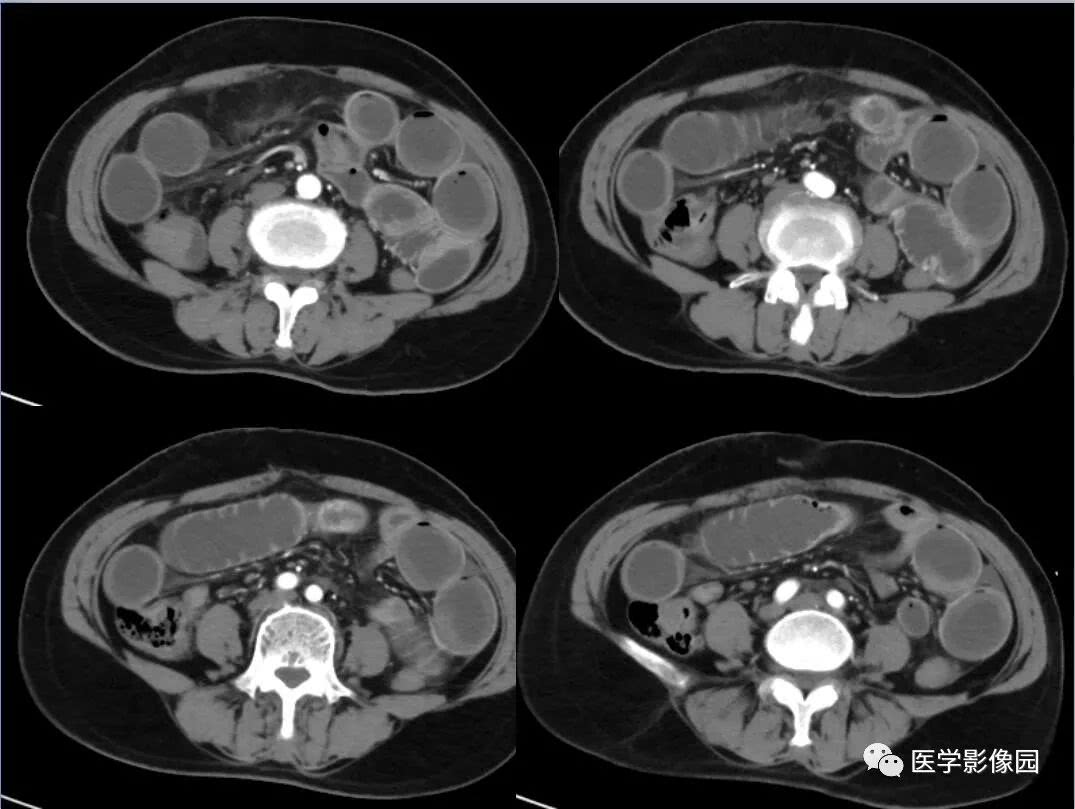

肠梗阻ct影像表现医学影像图

ct入门 | 肠梗阻的ct影像诊断